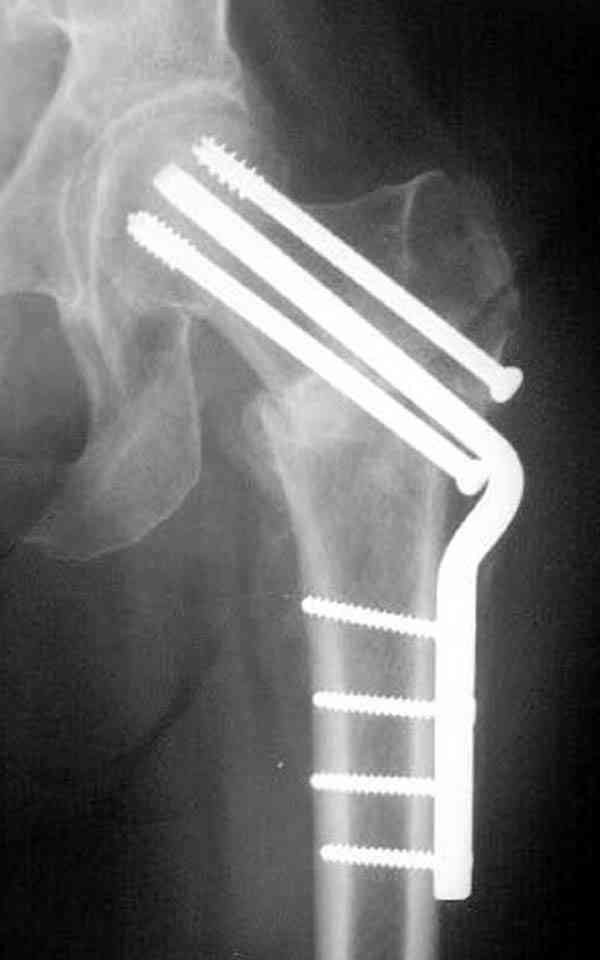

Здесь случай перелома из-за ослабления латерального кортекса через 3 недели после операции на шейке. Шурупы были установлены под большим углом, слабый латеральный кортекс не выдержал нагрузку.

Предлагая методику армирования, мы рассматривали вероятность ослабления кортикального слоя в месте проведения имплантата. В перспективе, эта проблема должна быть решена формой имплантата, путем добавления к винту диафизарной накладки длиной 6-8 см, через проксимальное отверстие которой будет введен канюлированный винт, в дистальной отверстие введен монокортикальный и лучше блокируемый винт диаметром не более 3,5 мм.